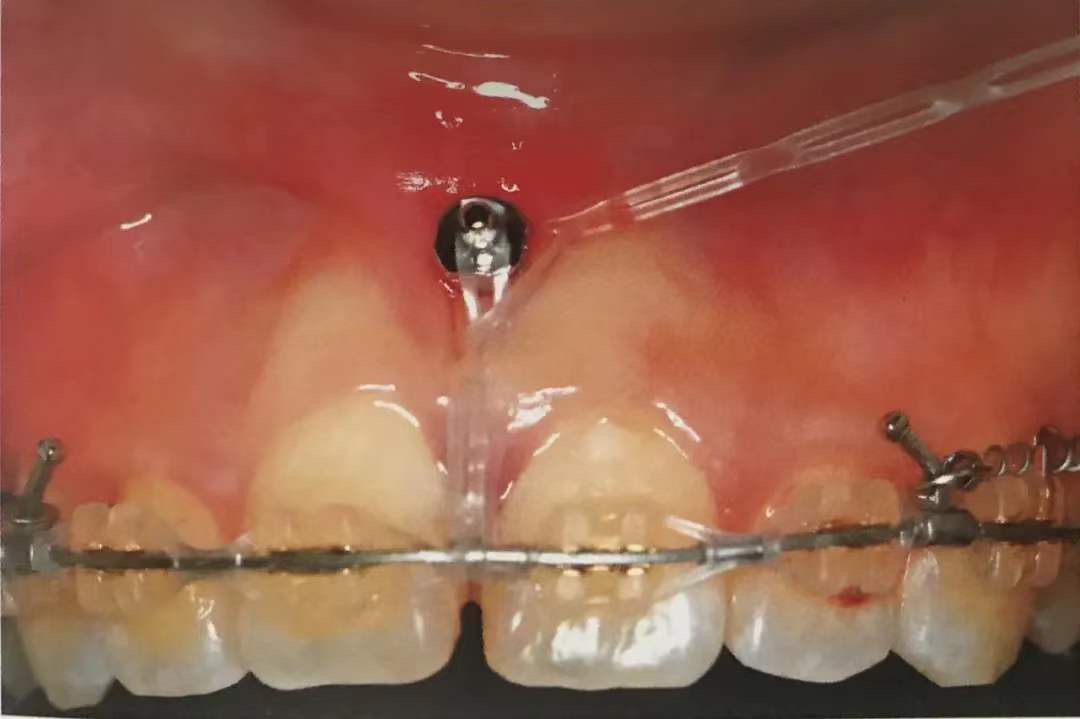

保持清洁,防止支抗钉脱落:术后如果黏膜周围炎或种植体周围炎发生,微螺钉失败的可能性很大,所以术后保持口腔卫生尤为重要。

刷牙时,务必使用牙刷将支抗钉附近清洁干净,最好轻柔牵拉开周围的黏膜,将其暴露出来,围绕着种植钉打圈圈刷干净,不要留有软垢。可使用间隙刷、冲牙器辅助清洁。